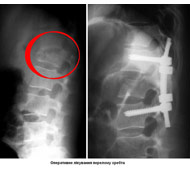

Мета операції - стабілізація хребта металевими конструкціями (імплантантами). Наша клініка була першою в СНД, яка застосувала сучасні конструкції при переломах хребта. Нині ми використовуємо імпортні конструкції типу CD Horison Legacy (США), Atlantis (США), Sextant (США), Socore (Франція). Операції вимагають складної рентгенівської техніки та спеціального інструментарію. При неускладнених переломах хребта хворі можуть ходити після таких операцій уже на другий - третій день. Також в Міжнародному центрі нейрохіургіі вперше в Україні впроваджено метод мініінвазивних операцій при переломах хребта.